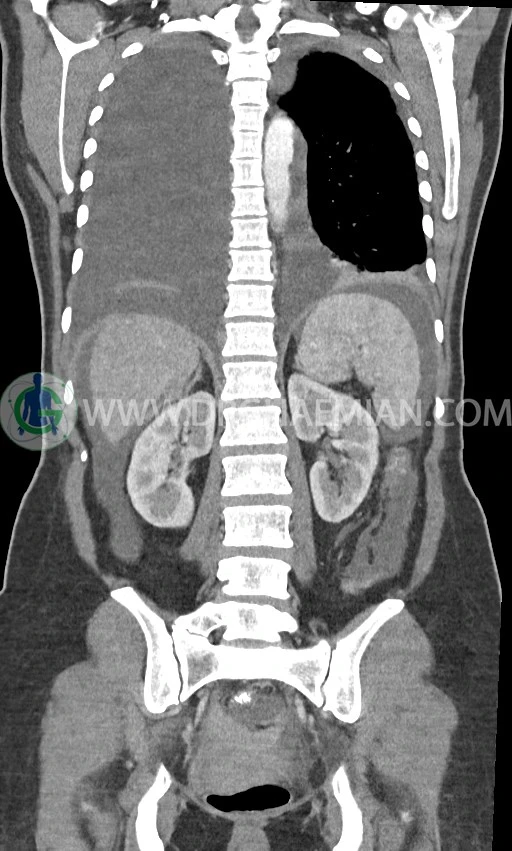

در سی تی اسکن اسپیرال ریه، مدیاستن و شکم و لگن با کنتراست خوراکی و وریدی (مولتی دیدکتور 16 با مقاطع ظریف و بازسازی های ساژیتال و کرونال) :

ضایعه ای در کبد، کیسه صفرا، مجاری صفراوی، طحال، کلیه ها، پانکراس و آدرنالها مشهود نیست.

کلیه ها کنتراست را ترشح کرده اند و نمای سیستم پیلوکالیسیل و حالب دو طرف نرمال است .

اسیت قابل توجه در حفره شکم و لگن

انفیلتراسیون تومورال در قسمت های مختلف اومنتوم (omental cake)، به ویژه در قسمت تحتانی حفره شکم و لگن

توده سالید – سیستیک به ابعاد 40x60mm در تخمدان چپ و به ابعاد 20x40mm در تخمدان راست و